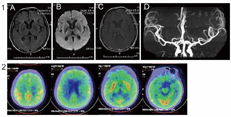

胸部CT示肺部感染,全腹CT未见明显异常。头MRI+DWI+增强+MRA:双侧额叶及侧脑室后角点状缺血灶,DWI未见弥散受限,脑萎缩,增强未见明显强化,颅内血管未见狭窄(图1)。18F-FDG-PET示全脑代谢减低,以双侧额叶、颞叶为著(图2)。视频脑电图示未见典型睡眠生理性纺锤、顶尖波及K复合波,双侧半球散在棘波、尖波(图3)。PRNP基因检测示:PRNP基因存在D178N突变,并与129Met连锁,129基因为Met纯合子(图4)。

FFI是一种罕见的、致死性的朊蛋白病,绝大多数为遗传性,但亦有散发病例报道。作为一种常染色体显性遗传性朊蛋白病,FFI通常由位于第20号染色体短臂上的、编码朊蛋白的PRNP基因突变所致。PRNP基因的密码子178发生错义突变(GAC>AAC),导致天冬酰胺替换天冬氨酸(D178N),同时伴有密码子129蛋氨酸的多态性改变(Met129)(即D178N-129M)。PRNP基因突变使神经细胞产生异常的且具有蛋白酶K抗性的PrPSC,致使丘脑及大脑皮层神经元变性而致病。FFI的年发病率大约为百万分之一,无性别差异。据报道,我国FFI患者发病年龄为21~68岁,中位年龄46.5岁,病程为6~38个月不等。该疾病突出的临床表现为睡眠障碍,表现包括失眠、睡眠相关不自主运动以及喉部喘鸣等,可同时伴有快速进展性认知功能下降、精神症状、锥体系及锥体外系受累表现以及自主神经功能障碍等[2,3],其中睡眠障碍通常贯穿整个病程。患者除失眠表现外,可伴有睡眠相关呼吸困难。可出现睡眠中的自动行为、幻觉及生动梦境;睡眠相关不自主运动,如入睡抽动、频繁变换体位、四肢不自主运动等。但FFI睡眠相关症状较为多变,部分患者可不表现为失眠。既往的病例总结发现,PRNP基因密码子129的基因多态性与患者临床症状及病程有关。密码子129纯合型(Met/Met)者病程更短,起病症状多为睡眠障碍,且自主神经功能障碍突出;而129杂合型病程较纯合型长,多以共济失调和构音障碍起病,运动障碍和括约肌功能障碍较为明显,且强直性肌阵挛较为常见。多导睡眠监测可显示睡眠结构改变以及睡眠期不自主运动等,对本病有较大的提示意义[4]。本病的头部MRI、脑脊液检查正常,脑电图未见典型睡眠生理性纺锤、顶尖波及K复合波,对诊断有一定提示意义。18F-FDG-PET上丘脑的代谢减低为本病的特征性影像学改变[5],对于该疾病的诊断具有重要作用。而该病的确诊依赖于PRNP基因检测,若结果显示PRNP基因存在D178N突变且伴有129密码子蛋氨酸多态性改变即可确诊为FFI[2,6]。

本病例特点为亚急性起病,快速进展性痴呆,伴有睡眠障碍、精神症状及运动障碍,体格检查显示意识障碍、喘鸣、锥体束征及锥体外系症状,无明确代谢、感染证据,视频脑电图未见典型睡眠纺锤、K复合波,PET显示全脑代谢减低,常规对症、抗感染以及免疫治疗均无效。提示存在朊蛋白病如CJD的可能。然而,该患者的辅助检查如头DWI及脑电图并不符合CJD特征性表现。由于朊蛋白病有数种类型,彼此之间的临床表型可能存在交叉,应考虑除CJD外的朊蛋白病。虽然该患者并无明确的家族史,仍可行PRNP基因检测辅助诊断。该患者PRNP基因检测结果符合FFI基因突变,且129密码子为Met纯合,得以确诊。本例患者睡眠障碍贯穿了全病程,且病程较短(约11个月),但自主神经功能障碍并不突出,提示该疾病的临床异质性。PET的丘脑代谢减低为该病的早期特征性表现,但患者PET显示全脑代谢减低,可能与患者病程有关。